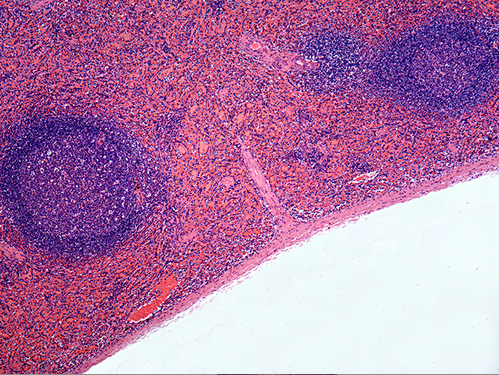

The artery at the end of the green arrow is the central artery of the spleen.

The dark area marked by the green arrow is

white pulp in the spleen.

This is an image of which lymphatic organ? spleen